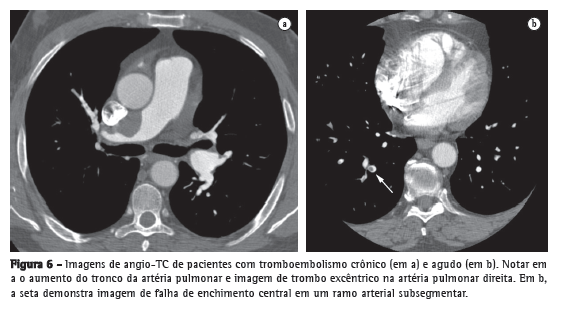

Pacientes com diagnóstico confirmado de HP apresentam alterações na radiografia de tórax em mais de 85% dos casos.(4) As principais alterações encontradas são aumento do calibre das artérias pulmonares no nível dos hilos, em 78% dos casos (Figura 1); afilamento periférico dos vasos, em 62%; e periferia pulmonar hiperlucente, em 9% (Figura 2).

O aumento do calibre das artérias pulmonares no nível dos hilos pode ser avaliado pela medida do diâmetro das artérias interlobares. O limite máximo do diâmetro transversal da artéria interlobar direita, medido de sua face lateral até a coluna de ar do brônquio intermediário, é de 16 mm em homens e de 15 mm em mulheres.(5) Devido à dificuldade de se realizar a avaliação da artéria pulmonar esquerda na incidência posteroanterior, deve-se avaliar o vaso na radiografia em perfil, partindo da transparência circular criada pelo brônquio do lobo superior esquerdo (que é visto telescopado), até a margem posterior do vaso que cavalga o brônquio; o limite máximo do normal é de 18 mm (Figura 1). O índice hilar torácico (soma da medida separada dos hilos pulmonares em relação ao diâmetro torácico total) maior do que 38% é classicamente descrito, e está presente em aproximadamente 75% dos pacientes com HP (Figura 1).(6) Raramente pode ser evidenciada a calcificação vascular, localizada geralmente no tronco da artéria pulmonar (TAP) ou em seus ramos hilares. Essa alteração é mais frequentemente relacionada a cardiopatias congênitas e embolia central crônica.

A radiografia de tórax pode auxiliar no diagnóstico diferencial com doenças do parênquima pulmonar, insuficiência cardíaca, DPOC e cifoescoliose, podendo levar a suspeita de doença tromboembólica pulmonar quando se notam áreas de oligemia, consolidações múltiplas sugestivas de infartos pulmonares ou assimetria entre as artérias pulmonares principais (Figura 2).(7)